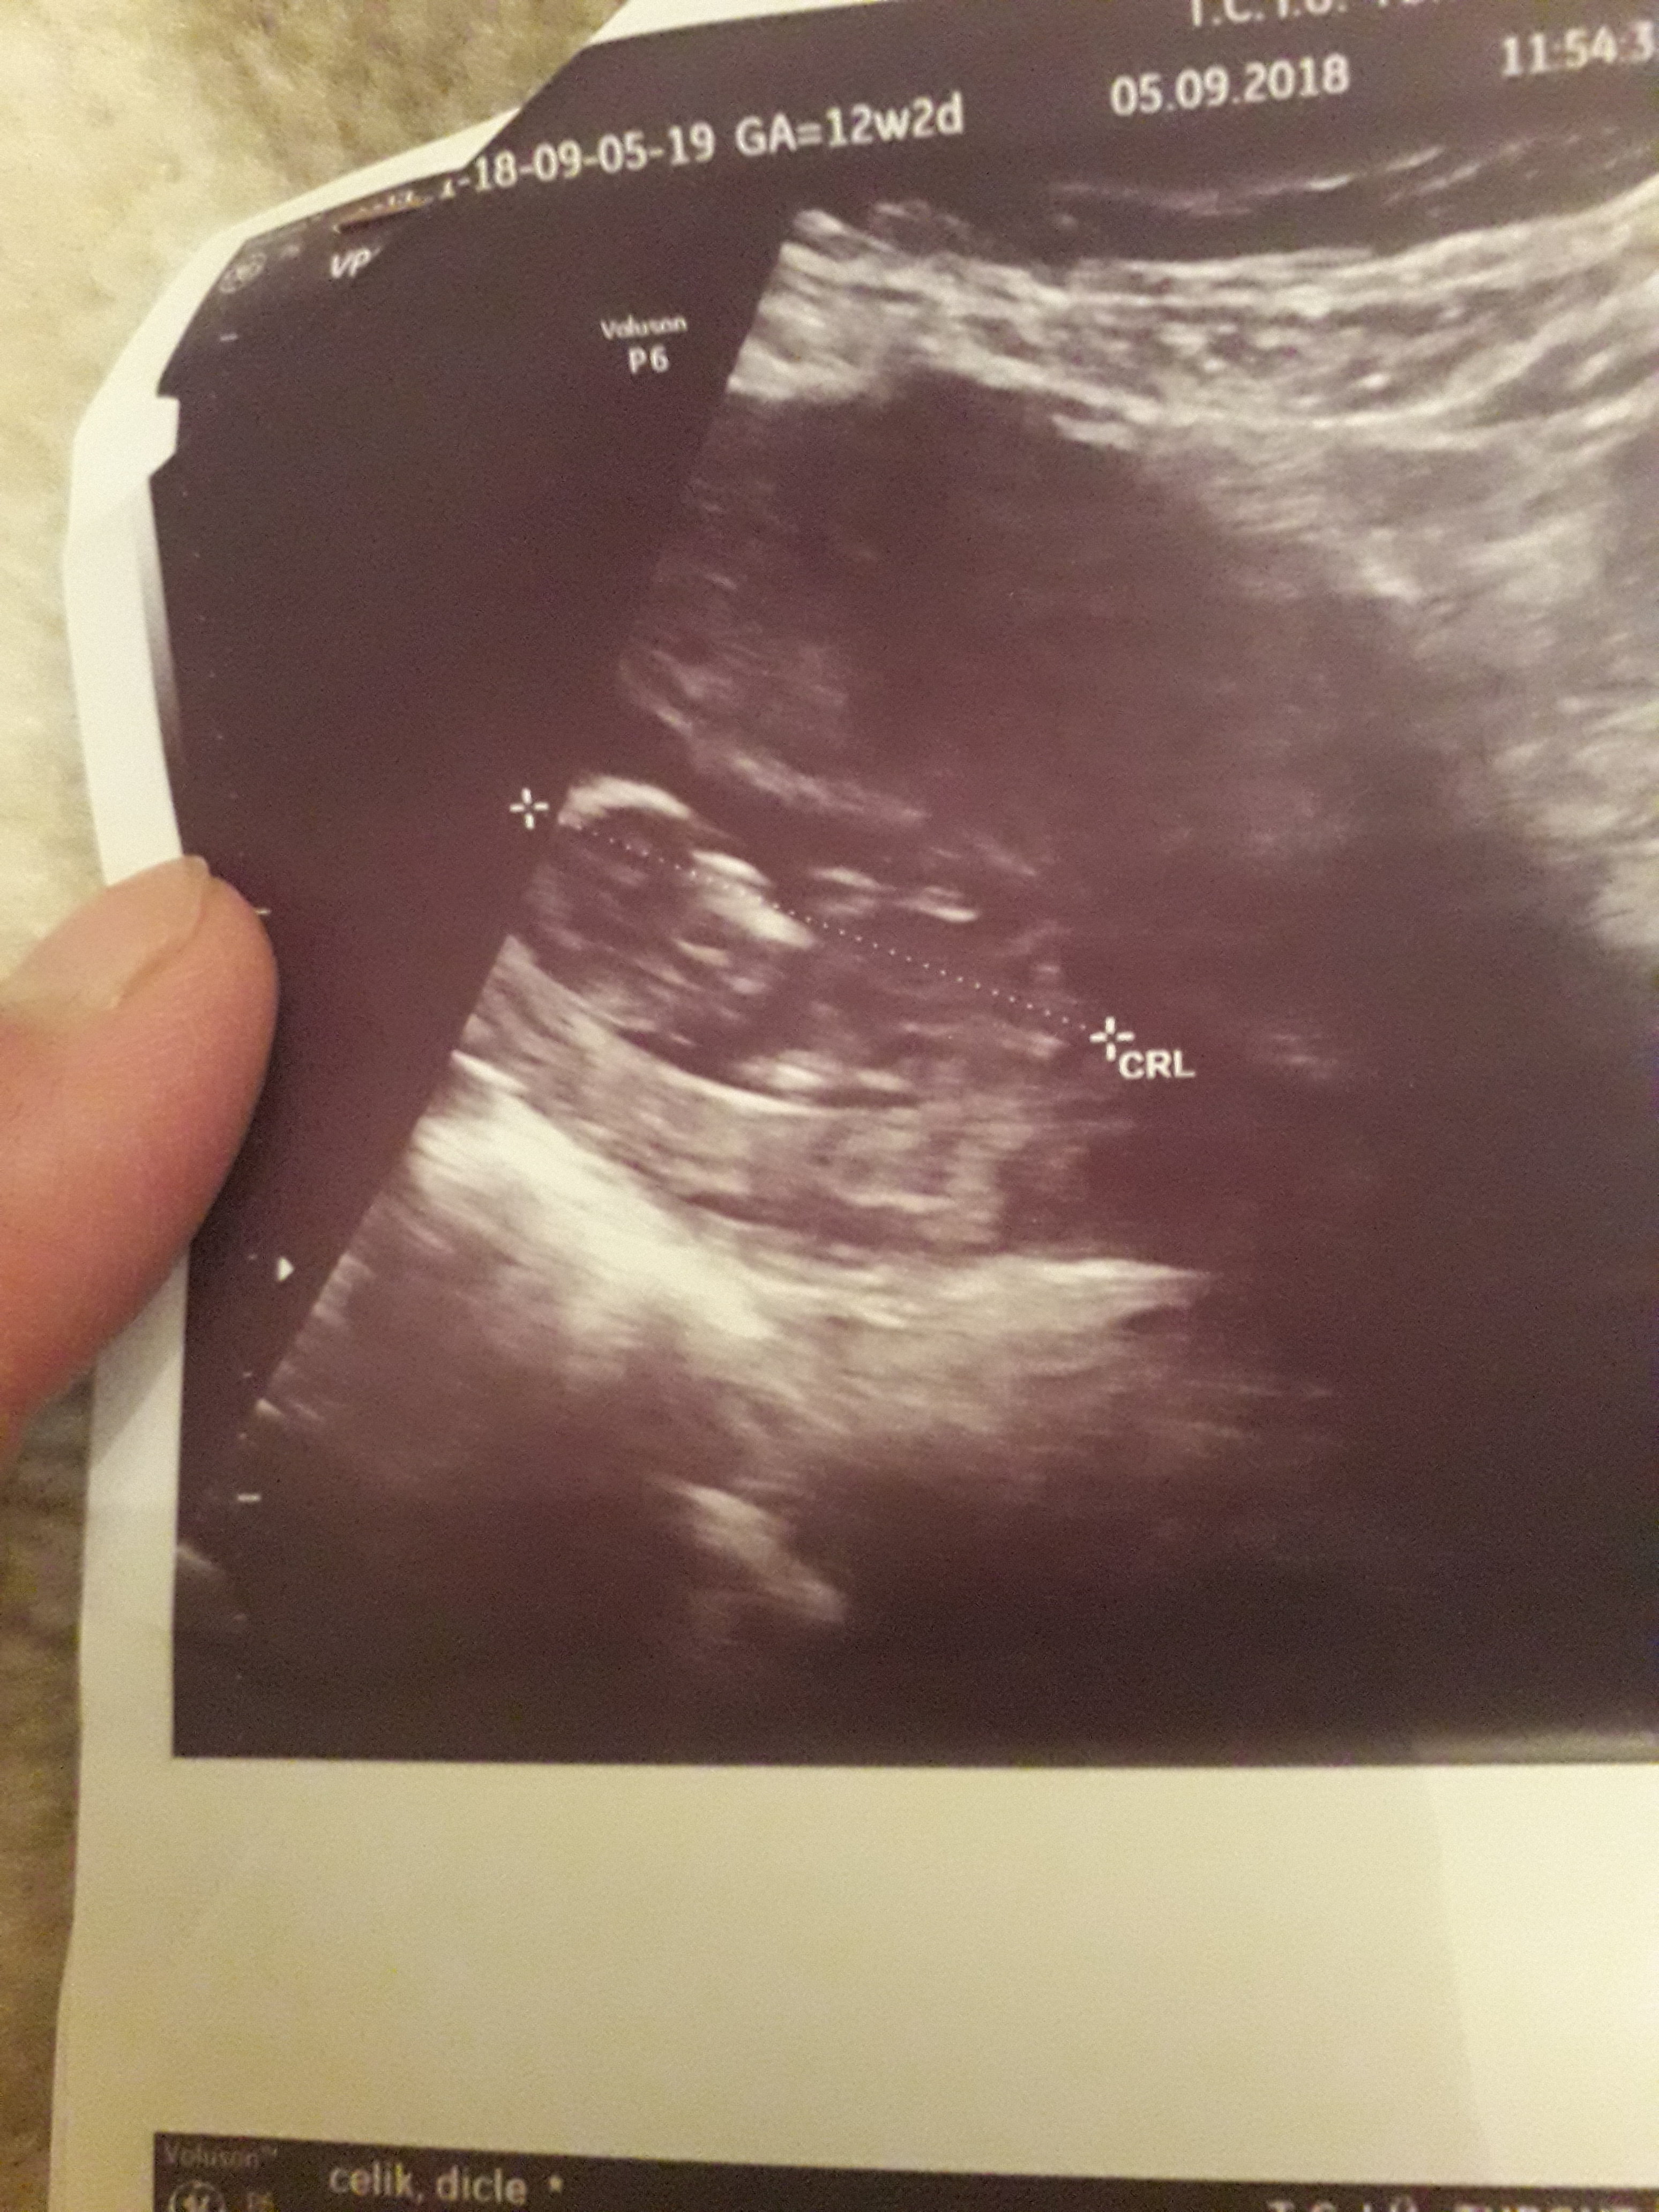

Dun malatyada verildi 12 +4 gunluk lutfen yorumlayin

nub çıkıntısının üzerinde imleç var cinsiyet anlaşılmıyor ilk sayfayı incelemenizi öneriyorum görselin kalitesi konu içinde yer alan görselle aynı olmalıdır.

Görsellerde nub çıkıntısı belli değil . Ultrasonu yapan doktor cinsiyeti hakkında bilgi vermiştir mutlaka ama şunu belirtmeden geçmeyeyim. Bu haftalarda cinsiyet tahmininde yanılma payı çok yüksek 17-19 ve 20 ci haftalarda bebeğin cinsiyetini net olarak öğrenebilirsiniz.